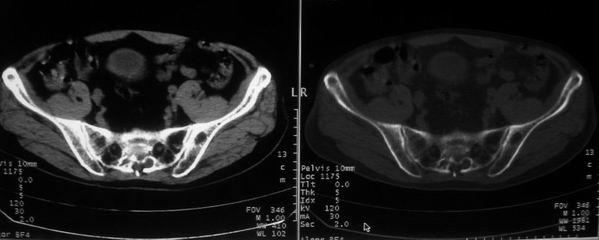

男,85岁,排尿困难。骶椎有问题吗?

1)考虑前列腺增生症并阻塞性膀胱炎。2)骶椎右侧类似囊状骨质密度减低区,边缘骨质硬化,其内为软组织密度影填塞,相邻之骶椎椎管受压变形;考虑为骶椎右侧囊肿或神经纤维瘤。

1)前列腺明显增大,突入膀胱,各叶比例协调,密度均匀,精囊腺及精囊角正常;考虑前列腺增生症并阻塞性膀胱炎。2)骶椎右侧类似囊状骨质密度减低区,边缘骨质硬化,其内为软组织密度影填塞,相邻之骶椎椎管受压变形;考虑为骶椎右侧囊肿或神经纤维瘤。

建议:行mri检查。